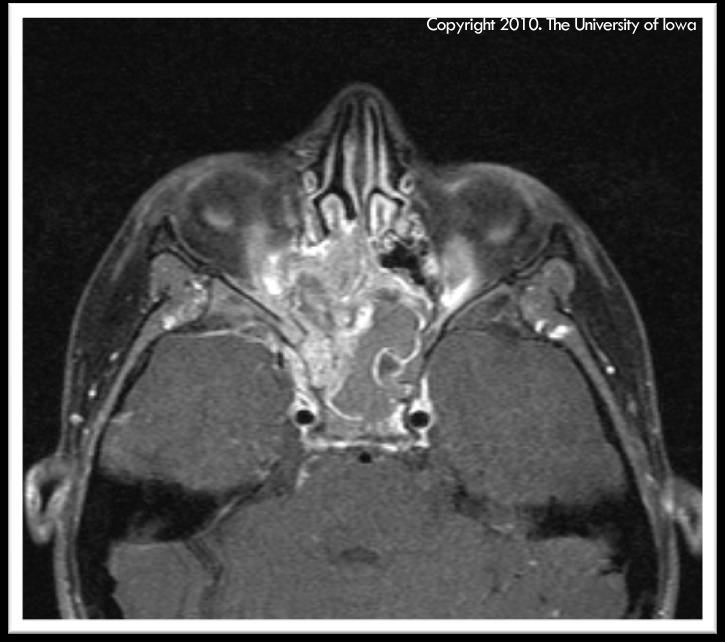

Rhabdomyosarcoma. EyeRounds.org - Ophthalmology - The University Of Iowa

webeye.ophth.uiowa.edu

webeye.ophth.uiowa.edu

rhabdomyosarcoma mri sphenoid ophth eyeforum webeye uiowa cases edu

rhabdomyosarcoma orbit 2010